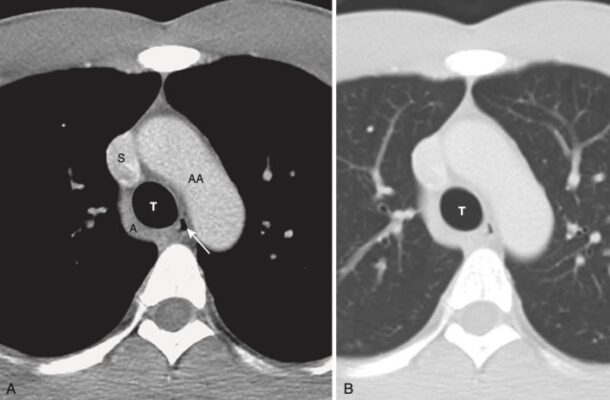

Mức cửa sổ chủ phế (Aortopulmonary Window) (Hình 7)

- Ở mức này, có thể xác định được động mạch chủ lên và xuống, tĩnh mạch chủ trên và (có thể thấy) mặt trên của động mạch phổi trái .

- Khi các lát cắt xuống thấp hơn qua lỗ mở chữ U lộn ngược của cung động mạch chủ, động mạch chủ lên sẽ có dạng tròn ở phía trước, trong khi động mạch chủ xuống sẽ có dạng tròn ở phía sau và bên trái của cột sống. Động mạch chủ lên thường có đường kính 2,5 đến 3,5 cm và động mạch chủ xuống nhỏ hơn một chút ở mức 2 đến 3 cm.

- Ở hầu hết mọi người, có một khoảng trống ngay bên dưới cung động mạch chủ nhưng ở trên động mạch phổi được gọi là cửa sổ chủ phế. Cửa sổ động mạch chủ là một mốc quan trọng vì đây là vị trí thường xuất hiện các hạch phì đại.

- Ở mức này hoặc thấp hơn một chút, khí quản chia đôi ở carina thành phế quản chính phải và bên trái.